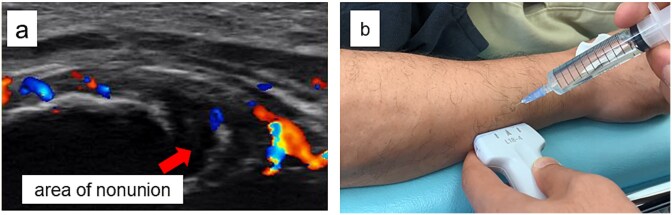

前驱疗法,包括注射高渗葡萄糖来刺激生长因子释放和促进组织愈合,最近作为一种难治性肌肉骨骼疾病的再生治疗得到了关注。我们报告一位54岁的男性,在空手道损伤后出现疼痛的尺干不愈合。保守治疗12个月后失败,患者出现持续性疼痛(数值评定量表[NRS]评分6)。超声引导下使用30%葡萄糖溶液进行前驱治疗,每2-3周进行5次。4周时发现骨痂形成,疼痛完全缓解(NRS评分0),患者在12周时恢复空手道训练。影像学证实15周愈合,无需固定或手术。这个病例强调了前驱疗法作为一种微创和有效的手术治疗疼痛性骨不连的替代方法的潜力。

Prolotherapy, involving hypertonic dextrose injections to stimulate growth factor release and promote tissue healing, has recently gained attention as a regenerative treatment for refractory musculoskeletal conditions. We report a 54-year-old man with a painful ulnar shaft nonunion after a karate injury. Conservative treatment failed over 12 months, and he presented with persistent pain (numeric rating scale [NRS] score 6). Ultrasound-guided prolotherapy using a 30% dextrose solution was performed in five sessions at 2-3 week intervals. Callus formation was noted at 4 weeks, pain completely resolved (NRS score 0), and the patient resumed karate at 12 weeks. Radiographic union was confirmed at 15 weeks without immobilization or surgery. This case highlights prolotherapy's potential as a minimally invasive and effective alternative to surgery for painful nonunion.